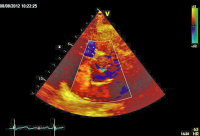

Parasternaler Längsschnitt

Abbildung 2: Parasternaler Längsschnitt mit Farbdoppler: Aorteninsuffizienz mit schmalem Jet (Vena contracta < 0,3 cm, < 25 % des LVOT).